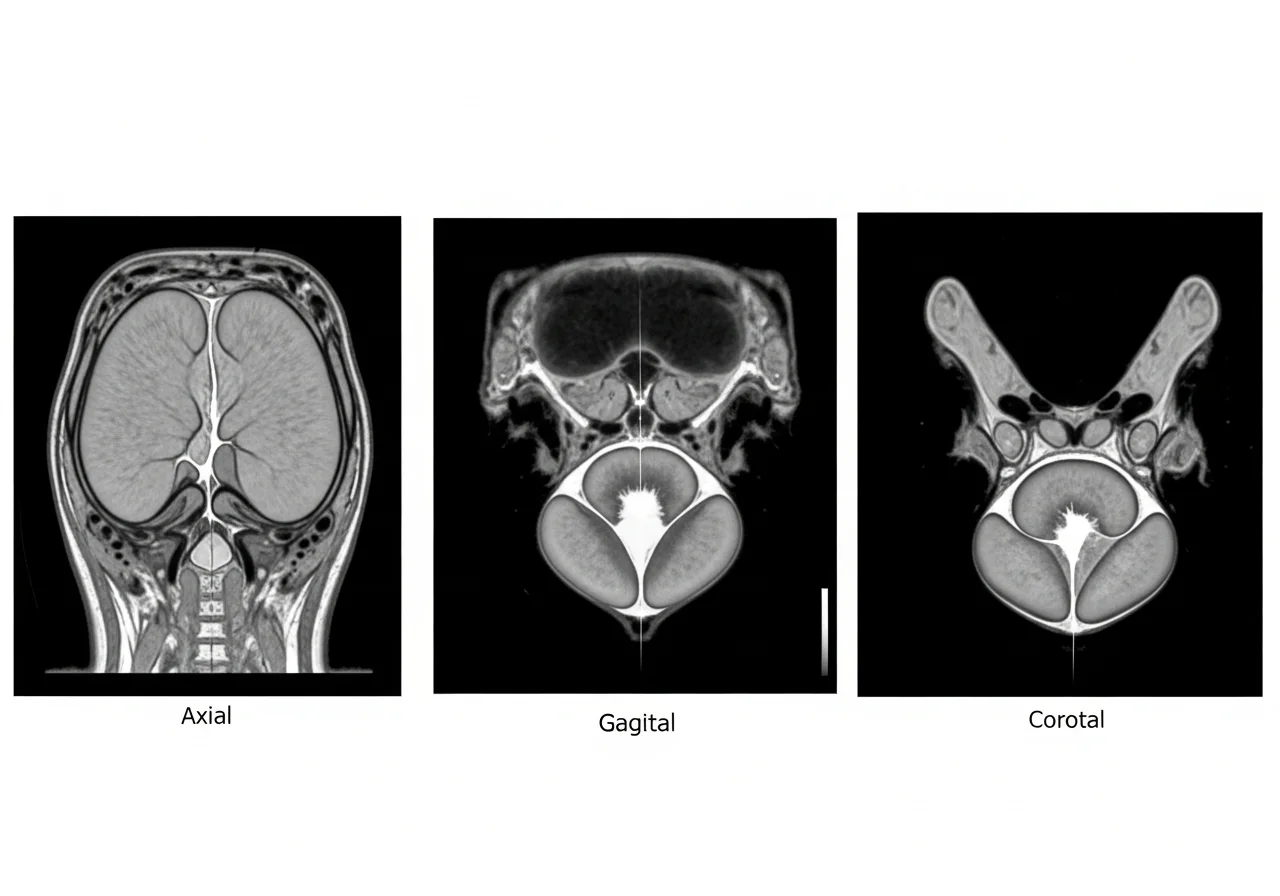

Magnetic resonance imaging, often performed as mpMRI, offers superior soft-tissue contrast.

MRI captures the prostate in multiple planes.

Axial, sagittal, and coronal views provide complete anatomy.

MRI also uses the ellipsoid formula in most clinical workflows.

However, landmarks are easier to define.

Strengths of MRI

MRI visualizes the prostate apex and base clearly.

This improves length measurement.

It reduces interobserver variability.

Different readers produce more consistent results.

MRI shows stronger correlation with surgical specimen weight.

This makes MRI prostate volume more accurate.